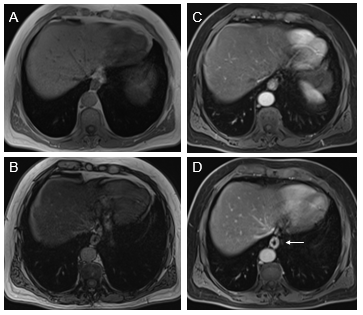

Jejunum: We have observed three patterns of jejunal increased enhancement: patchy discontinuous increased enhancement (seen most often on both arterial and venous phase images) (Figure 4); uniform increased enhancement on both arterial and venous phase images; and late venous phase serosal enhancement. This last phase can occur together with the other two patterns. Associations with the late serosal enhancement include mesenteric panniculitis (mesenteric panniculitis is always associated with late serosal enhancement, but mesenteric panniculitis is relatively uncommon in the setting of late serosal enhancement, maybe 10-20% of cases. Our current opinion is that small pancreatic cysts are observed in individuals with late serosal enhancement. Overall, our opinion is that inflammation spreads from the jejunum to the mesentery, causing mesenteric panniculitis (Figure 4) and to the pancreas, resulting in cysts and IPMNs. On occasion in moderate and greater severity inflammation, the adjacent descending colon also shows sympathetic inflammation.

Figure 4 Increased jejunal enhancement and mesenteric panniculitis. Axial T1-weighted out-of-phase (a), pre-contrast (B), arterial phase (C), and interstitial phase (D) images. Out-of-phase images (A) exhibited the greatest clarity for depicting mesenteric panniculitis. On out-of-phase images, the mesenteric fat is mild gray in signal (arrow, A) and has definable margins against a background of higher signal peritoneal fat. Occasional subcentimeter lymph nodes are commonly seen. Note on arterial phase image the mesenteric panniculitis is only minimally evident. Note the increase spacing of jejunal loops (similar to fatty proliferation in Crohn's disease) and the enhancement of bowel is readily seen in the arterial images (C) which become more evident in interstitial phase images (arrow, D).